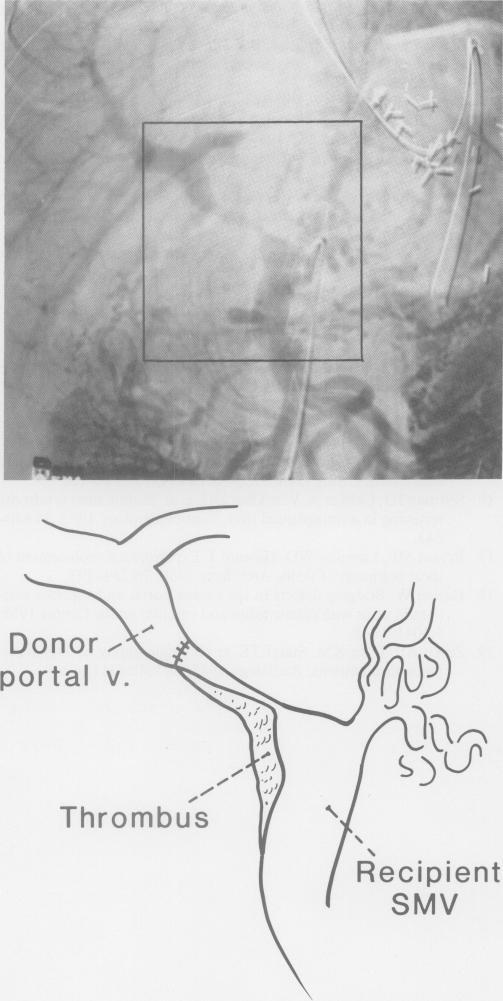

In 313 consecutive recipients of 393 orthotopic liver grafts, there were 51 (16.3%) and nine (2.9%) patients who had pre-existing portal vein and inferior vena cava abnormalities, respectively. These abnormalities required adjustments in the transplant operation and were a source of morbidity and mortality. The incidence of thrombosis of the reconstructed portal vein was 1.8%. Only three (0.8%) vena caval thromboses were seen after 393 liver replacements. Venous stenoses or disruptions were rare. Six women with the Budd-Chiari syndrome had liver replacement. Although this disorder is a veno-occlusive disease, five of the recipients achieved prolonged survival, only one had recurrence of disease, and three are alive after 2-6 years.

在313例接受393例原位肝移植的连续患者中,分别有51例(16.3%)和9例(2.9%)患者术前存在门静脉和下腔静脉异常。这些异常需要对移植手术进行调整,并且是发病和死亡的一个原因。重建门静脉血栓形成的发生率为1.8%。在393例肝移植术后仅发现3例(0.8%)腔静脉血栓形成。静脉狭窄或中断很少见。6例患有布加综合征的女性接受了肝移植。尽管这种疾病是一种静脉闭塞性疾病,但5例受者获得了长期生存,仅1例疾病复发,3例在2至6年后仍存活。